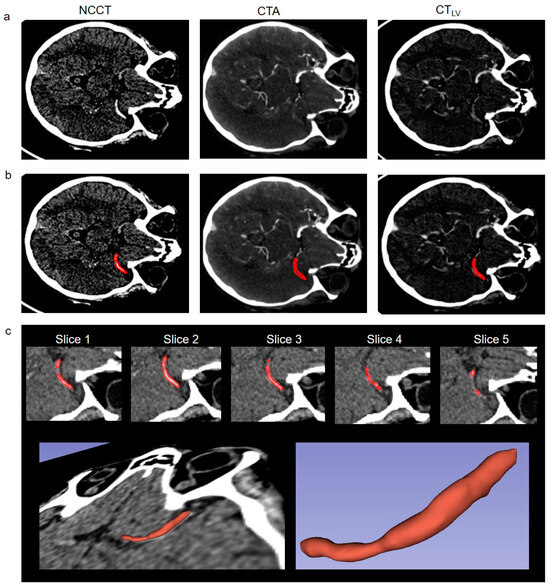

2.2. Imaging

2.3. Image Processing and Statistical Analysis